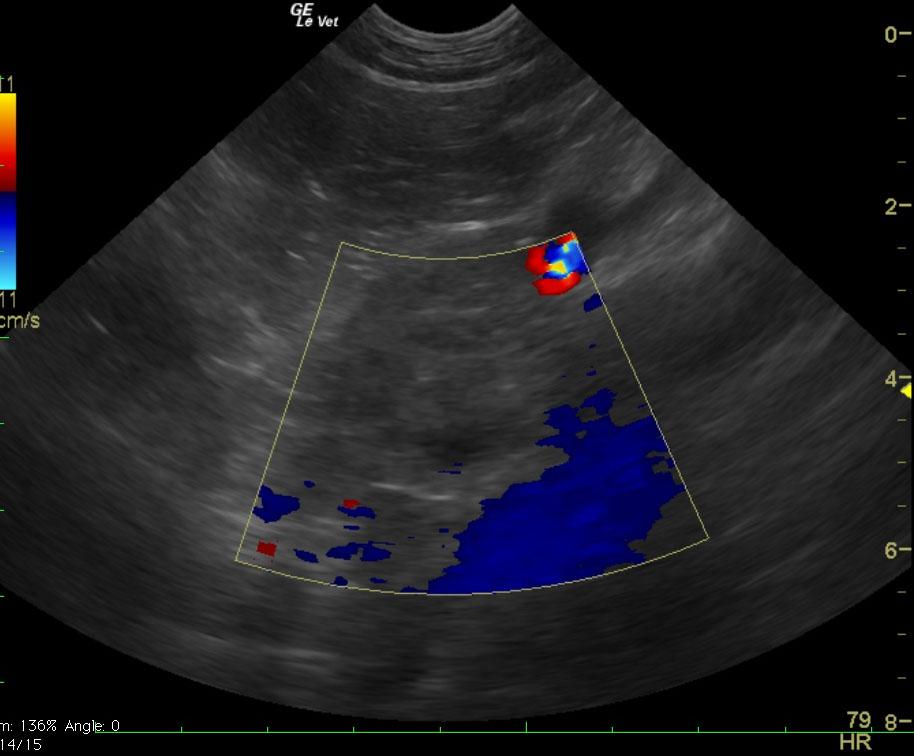

The patient is a canine Golden Retriever, NM, 11 years old. The patient was presented for a recheck exam to follow up a right adrenal tumor. The prior ultrasound revealed hepatic cyst that measured 2.1 x 2.04 cm and a separate cyst that measured 1.08 x 0.84 cm in the left liver. A separate nodule in the left liver measured 0.8 x 0.7 cm. The prior measurements of the adrenal gland were 2.5 x 0.65 cm at the cranial pole and 2.1 of the caudal pole of the right adrenal gland without vascular invasion. There was a pericapsular inflammatory pattern of the right adrenal gland that measured 2.7 x 0.4 cm. Patient is now PU/PD. An ACTH stim was inconclusive.